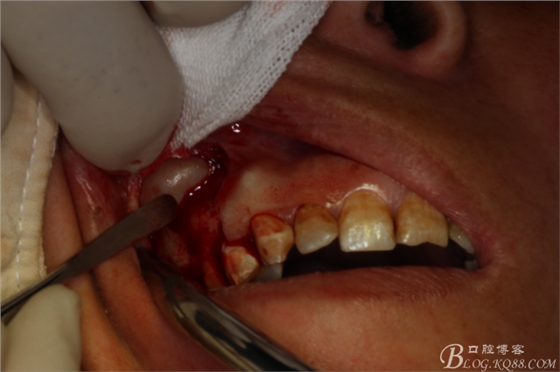

圖5.唇側(cè)局部浸潤(rùn)麻醉

圖7.做角形切口